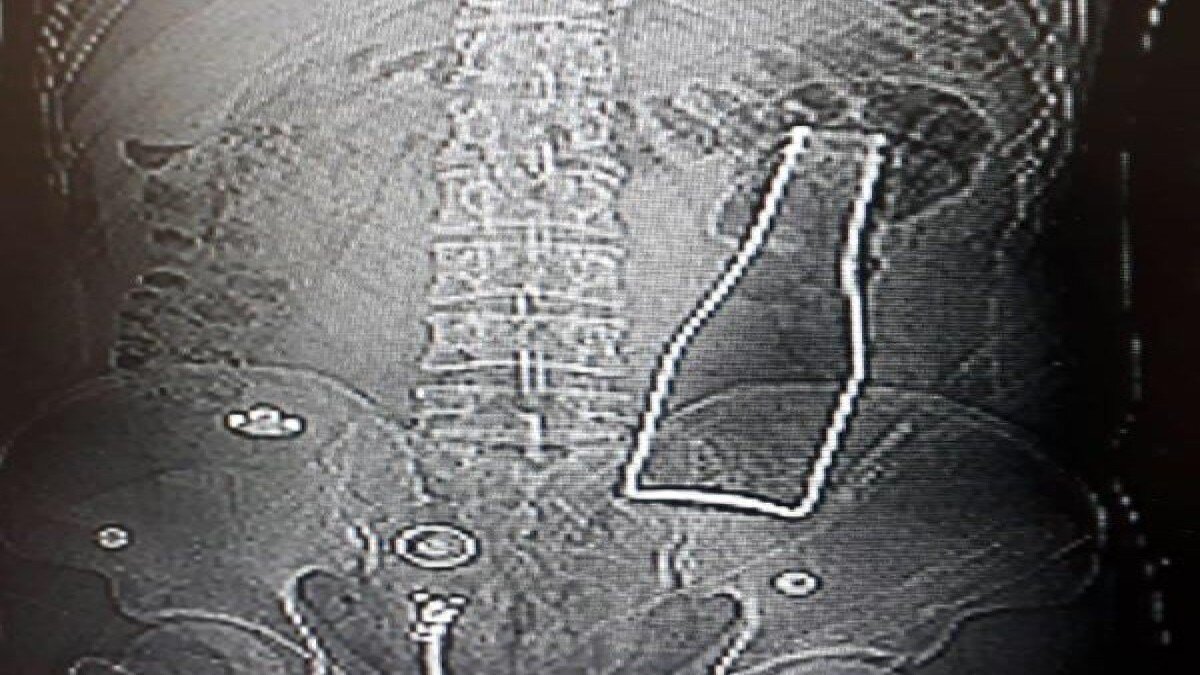

Karaman'da karın ağrısı şikayetiyle hastaneye giden Afganistan uyruklu A.E. adlı erkeğin, çekilen röntgen filminde beklenmedik bir durumla karşılaşıldı.

Röntgene yansıyanlara göre, A.E.'nin kalın bağırsağında şişe olduğu ortaya çıktı.

27 yaşındaki A.E.'nin makatından sokulduğu belirtilen soda şişesi, yaklaşık 1 saat süren ameliyatla alındı. A.E.'nin olayla ilgili verdiği ifade belli oldu.